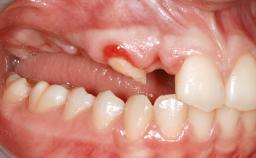

A 20-year-old woman was referred for implant therapy in 2004. Her medical history revealed no significant findings, and neither did she smoke nor take any medications. An extraoral examination revealed no abnormalities of the skin, hair or nails. The intraoral examination revealed only 11 permanent teeth clinically. These were normal in shape, size, and color. In addition, eight retained deciduous teeth (53, 62, 63, 71, 72, 73, 81, 82) were present. No abnormalities were detected during the general examination. The family history revealed that the patient’s father and two sisters were on record with similar conditions. The clinical examination revealed a thick gingival biotype. No recession of the attached gingiva was noted, but the retained deciduous teeth were mobile and unsightly. As a syndrome had not been diagnosed, the case was categorized as non-syndromic oligodontia.

Soft Tissue Anatomy Intact Defective

Bone Volume Horizontally and vertically sufficient Horizontally deficient Deficient vertically or deficient vertically AND horizontally